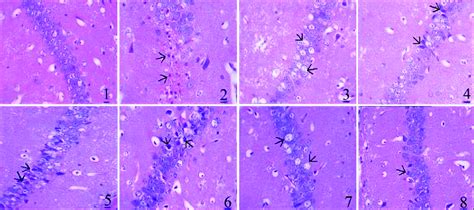

• CA1 Region Of Hippocampus Histopathology Of Various Groups (400Â ). (A ...

• Photomicrographs Of The CA1 Region In The Dorsal Hippocampus Across ...